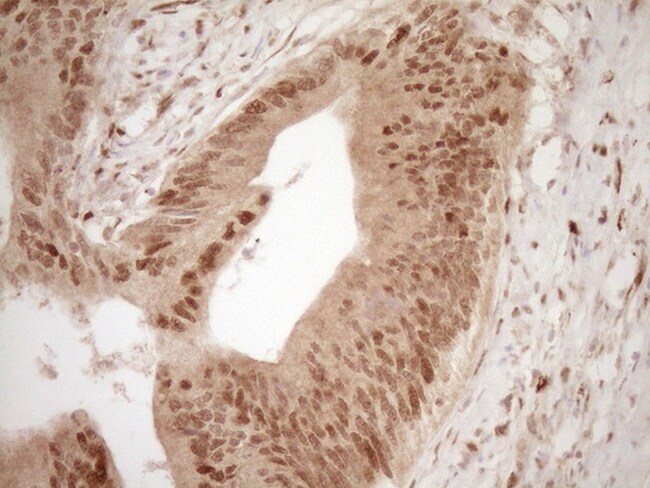

Supportive validation

- Submitted by

- Invitrogen Antibodies (provider)

- Main image

- Experimental details

- Immunohistochemical staining of paraffin-embedded human colon tissue within the normal limits using anti-GFI1 mouse monoclonal antibody. (Heat-induced epitope retrieval by 1 mM EDTA in 10mM Tris, pH8.5, 120°C for 3min, TA805544)